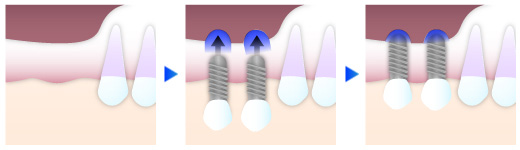

② 即日埋入のインプラント治療にも対応

インプラント治療は通常、抜歯を行ってから最終段階の人工歯を被せるまでに、約6ヶ月間待機時間が必要となります。当院では、患者様の口内条件などが揃った場合に、「抜歯即時負荷法」と呼ばれる術式で、抜歯後すぐに仮歯まで装着ができる治療法に対応しています。

インプラント治療は通常、抜歯を行ってから最終段階の人工歯を被せるまでに、約6ヶ月間待機時間が必要となります。当院では、患者様の口内条件などが揃った場合に、「抜歯即時負荷法」と呼ばれる術式で、抜歯後すぐに仮歯まで装着ができる治療法に対応しています。

歯がない期間をなくす事が出来るだけでなく治療時間やご来院頻度も軽減できて負担を抑える事ができます。ご希望の方はぜひ、ご相談下さい。